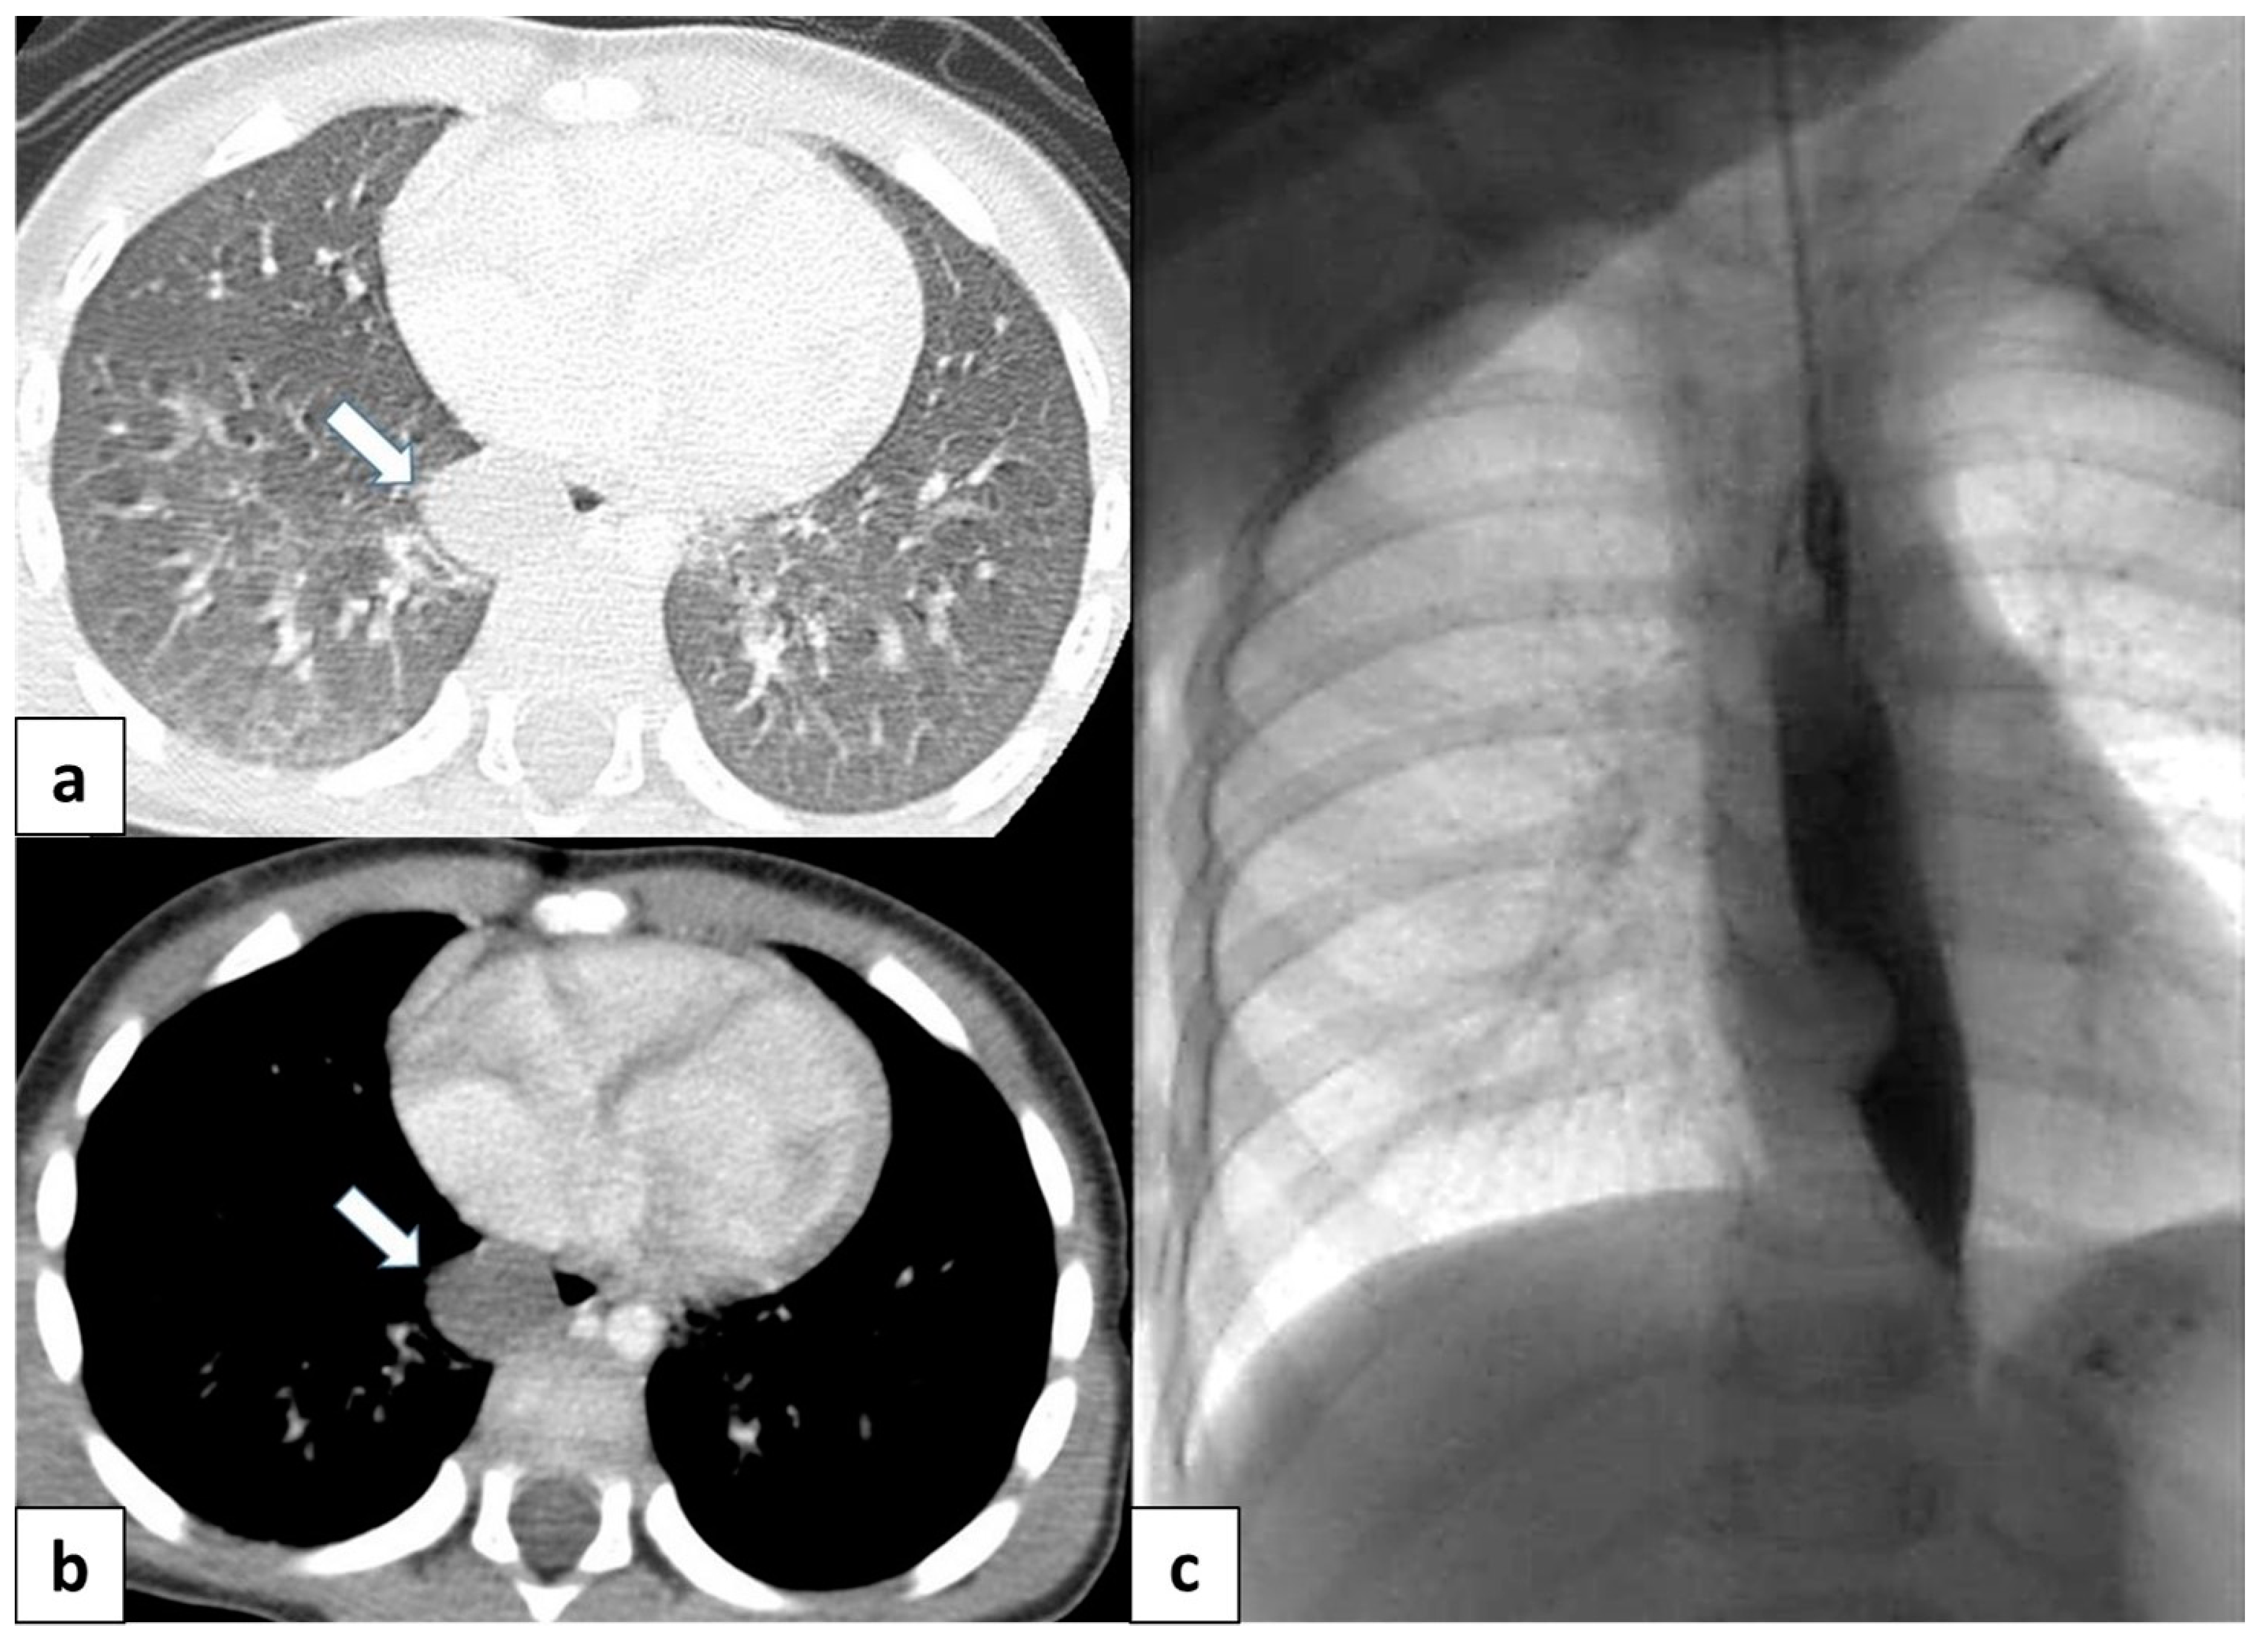

Figure 11.

(a) CT scan in a 6 month old child shows a well-defined, rounded lesion with uniform fluid attenuation (arrow), compatible with a bronchogenic cyst; (b) after administration of intravenous contrast, bronchogenic cyst shows no enhancement or a minimally enhancing wall (arrow). (c) Dynamic esophageal fluoroscopy with oral contrast administration revealed a round, filling defect within the esophageal lumen, indicating that the cyst arises extrinsically from the bronchial tree.

CT helps to evaluate density, the extension of the lesion, and its relationship with the adjacent structure, as well as to differentiate bronchogenic cysts from vascular abnormalities using intravenous contrast [3,15]. CT scans reveal well-defined, smoothly contoured, and rounded lesions with uniform fluid attenuation, although the CTHU attenuation value varies depending on the concentration of proteinaceous elements (Figure 11a,b). Following intravenous contrast administration, bronchogenic cysts typically do not present with signs of enhancement or at most a mildly enhancing wall [15] (Figure 11b).

The presence of an internal air–fluid interface or a markedly thickened wall demonstrating intense contrast enhancement may suggest a secondary infection [15].